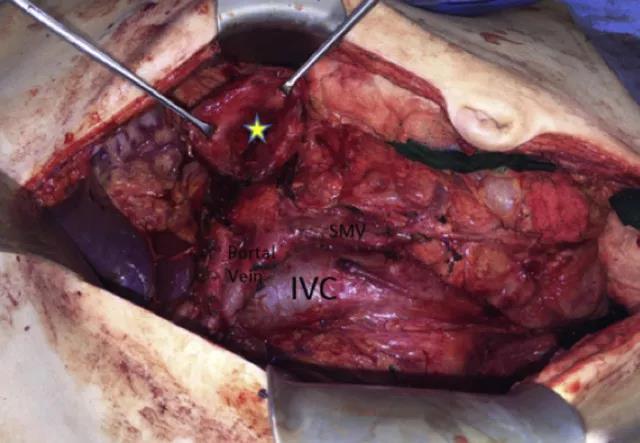

体格检查发现右上腹有一质软肿物(图 1)。

图 1  体检发现右上腹包块(黄色星号所示)

随后予施行胰十二指肠切除术,术中证实为肿瘤堵塞胰管,导致胰管直径扩张至 17 cm,伴有腺体肥大(图 3)。